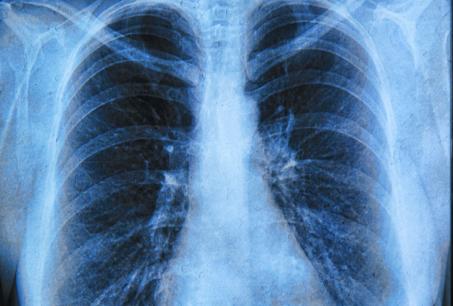

Profiling approach to enable right lung cancer treatment match

Manchester researchers have tested a new way to genetically profile lung cancer samples, potentially allowing doctors to more easily identify the most appropriate treatment for patients.

Non-small cell lung cancer (NSCLC) represents over 85% of lung cancer cases. The recent introduction of targeted therapies has led to improved patient survival, but only patients whose tumours have a specific genetic change are eligible for such treatments.

Identifying individual patients who may benefit from targeted therapy is becoming an essential part of treatment planning, but many current genetic analysis methods such as next generation sequencing require relatively large amounts of tumour material.

Dr Fiona Blackhall, a senior lecturer in The University of Manchester's Institute of Cancer Sciences and a consultant based at The Christie NHS Foundation Trust -- both part of the Manchester Cancer Research Centre -- said: "Unfortunately the biopsy samples we take from these patients are generally quite small. In this study we looked at an alternative genetic screen that utilises a much smaller tissue biopsy to see if it can detect a range of changes in 26 key genes."

The Lung Cancer research group working with the Manchester Centre for Genomic Medicine used the LungCarta platform to screen tumour samples from 90 NSCLC patients. They found that they could analyse over 95% of the samples and they detected genetic changes (mutations) that could be used for selection of treatment in around half of the biopsy samples.

"This type of genetic testing appears to be a clinically useful diagnostic screening test that can be used on small biopsy samples. This should allow us to better match lung cancer patients to the right treatment and we have now started to use this method of testing to identify suitable clinical trials for our patients," added Dr Blackhall.